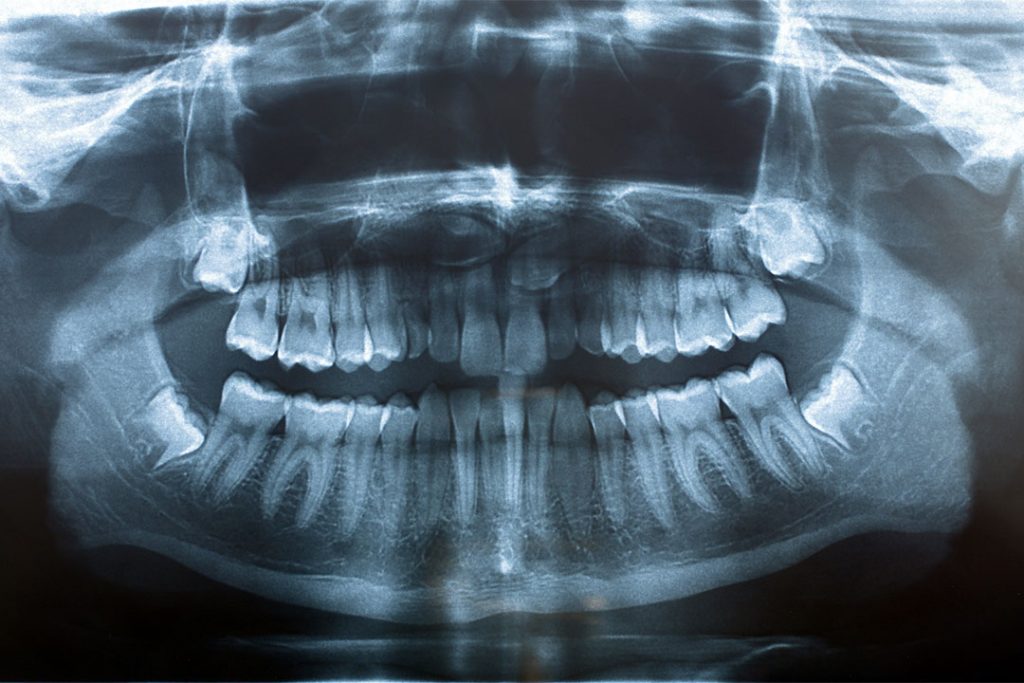

Röntgenbild